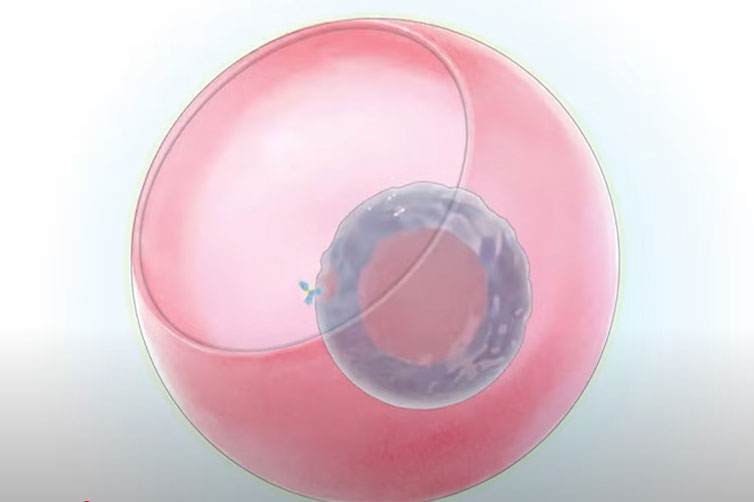

Better treatments for infertility

UCLA reproductive scientist Amander Clark is advancing infertility treatments by studying how stem cells develop into egg and sperm precursors, aiming to create functional reproductive cells in the lab.